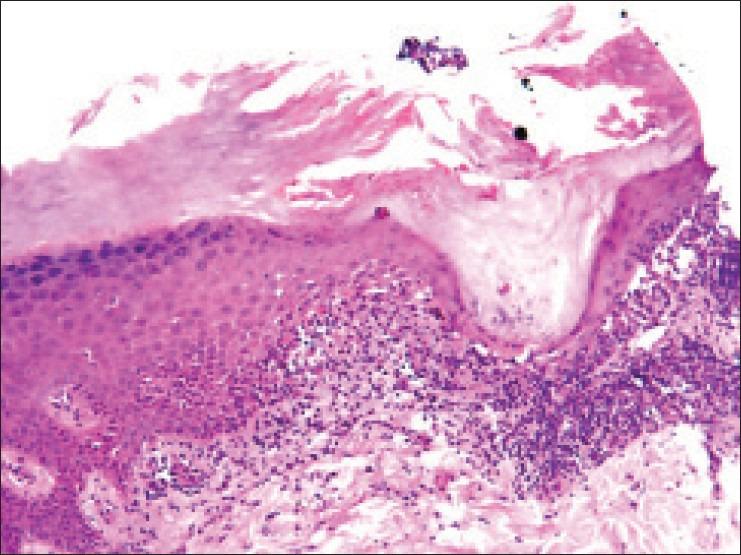

Lichen planus (LP) is a pruritic, benign, papulosquamous, inflammatory dermatosis of unknown etiology that affects either or all of the skin, mucus membrane, hair and nail. It presents with varied morphology on the palms and soles. Here we present a case of unusual acrosyringeal variant of LP on palm. The diagnosis was confirmed histologically.

扁平苔藓(LP)是一种病因不明的瘙痒性、良性、丘疹鳞屑性炎症性皮肤病,可累及皮肤、黏膜、毛发和指甲中的一个或全部。其在手掌和足底表现出多样的形态。在此,我们报告一例手掌部罕见的顶泌汗腺导管型扁平苔藓病例。组织学检查确诊了该诊断。